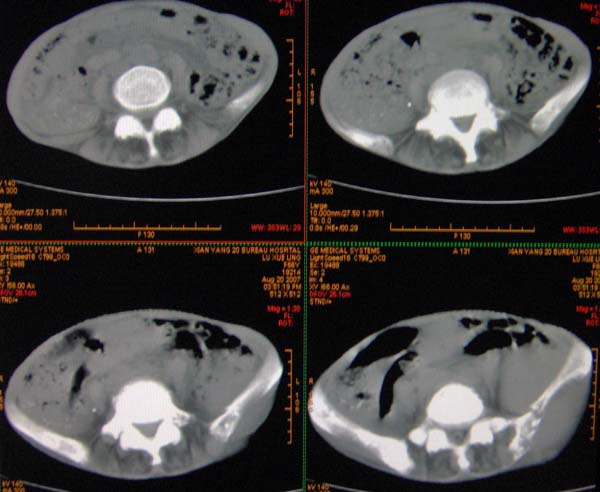

以下是引用ybing在2007-8-22 20:31:00的发言:[br]左侧髂骨溶骨样破坏;软组织肿块形成;其内未见肿瘤骨考虑纤维肉瘤或滑膜肉瘤不除外转移瘤

以下是引用qiushi在2007-8-22 21:39:00的发言:[br]双侧髂骨、骶骨侧快呈溶骨样骨质破坏,边缘模糊,左侧髂骨见骨折线,左侧髂部见软组织块影。考虑骨纤维肉瘤(中央型)伴病理性骨折,不排除骨髓瘤。建议本--周氏蛋白检查。[br] 鉴别点:[br] 骨纤维肉瘤,中央型者示边缘模糊的囊状溶骨破坏,一般无骨膜反映,可膨胀变形,突破骨皮质可形成软组织肿块,或并发病理性骨折。[br] 骨髓瘤,常表现为广泛的骨质疏松,皮质变薄或破坏,呈粟栗状、穿凿状、鼠咬状骨质破坏,边缘清晰,周围无硬化。[br] 骨转移瘤(溶骨型),表现为虫噬样、泡沫状圆形或卵圆形破坏区,很少出现软组织块影。[br][br][本贴已被 qiushi 于 2007-8-23 6:20:19 修改过]